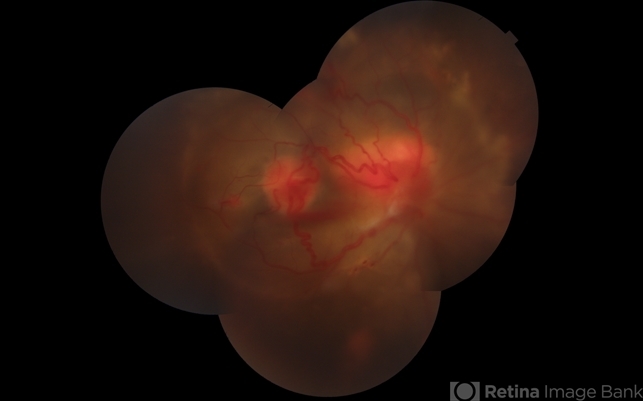

- Von Hippel-Lindau, exudative detachment

- 8 Year old child with Multiple Capillary Haemangiomas with Exudative retinal detachment.